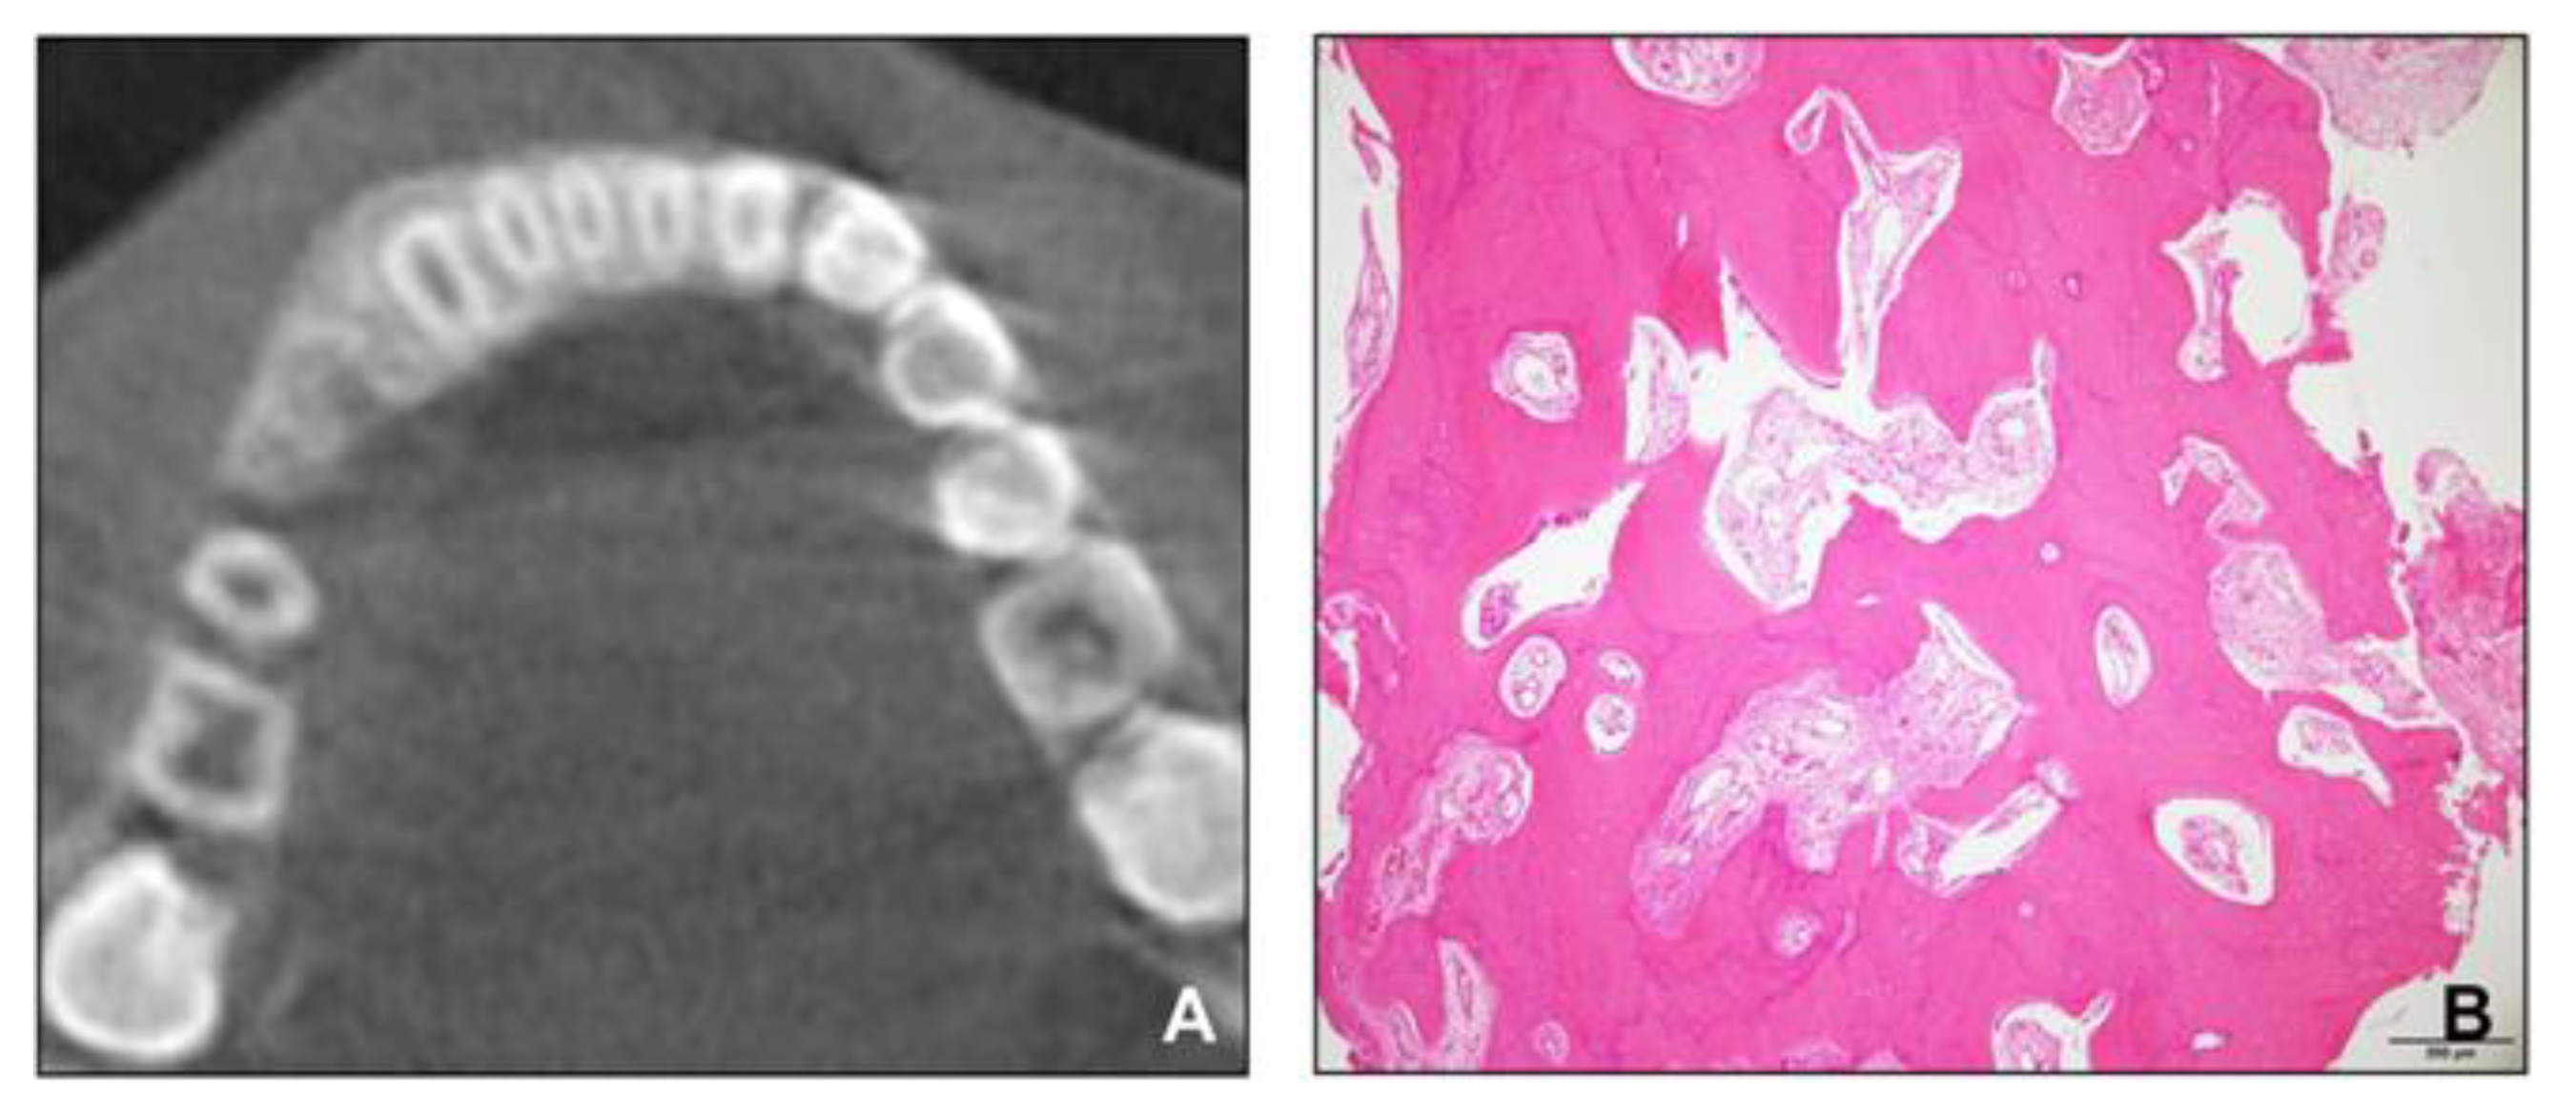

However, the hypertrophic region of the alveolar bone in the anterior mandible did not disappear. We referred the patient to the oral and maxillofacial surgery department for the re-evaluation of the hypertrophic region and for the extraction of the impacted supernumerary tooth in the right mandible. A cone-beam computed tomography scan was conducted, and a biopsy of the hypertrophic region was performed. The radiologic and histopathologic findings revealed that the lesion consisted of mature cancellous bone and had no pathologic features (Figure 6). After extracting the supernumerary tooth, we decided to closely follow up the patient for observing the growth.

Figure 6. (A) Cone-beam computed tomographic image; (B), Histopathologic image showing mature cancellous bone.

For patients similar to the patient in this case, one of the most important considerations is to determine whether the hypertrophic area has a progressive feature, such as fibrous dysplasia, prior to the start of the orthodontic treatment. The biopsies of other patients with maxillary alveolar bone hypertrophy have revealed non-specific, non-inflammatory tissues, which were different from the findings in other pathologic diseases, such as fibrous dysplasia [24]. In particular, differentiating diagnosis from fibrous dysplasia is important because in the case of McCune–Albright syndrome, café-au-lait spots can be present along with fibrous dysplasia [25]. In our patient, the radiographic image of the involved area revealed mature cancellous bone in contrast to the “ground-glass” patterns of fibrous dysplasia [26]. In addition, consistent with the previous reports showing non-specific, non-inflammatory connective tissue hyperplasia, no pathologic features were observed in histopathology [24], and the size of the lesion was stable during the observation period. Therefore, based on these results, we decided to start phase 2 treatment, and it was possible to finish it with reasonable outcomes.